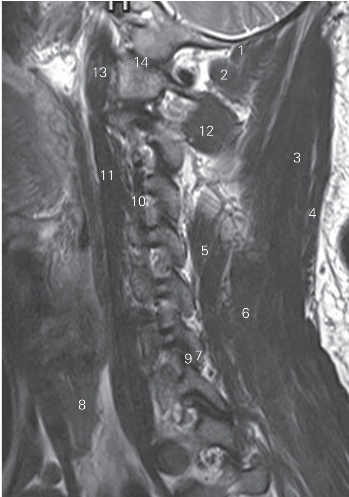

图1-6 经脊柱颈段旁正中矢状断层MR T2加权图像

1 头后小直肌 rectus capitis posterior minor

2 头后大直肌 rectus capitis posterior major

3 夹肌 splenius 4 斜方肌 cucullaris

5 颈半棘肌 semispinalis scervicis 6 头半棘肌 semispinalis capits

7 下关节突 inferior articular process 8 甲状腺 thyroid gland

9 关节突关节 zygapophyseal joint 10 椎动脉 vertebral artery

11 颈长肌 longus colli

12 头下斜肌 obliquus capitis inferior 13 头长肌 musculus longus capitis

14 寰枕关节 atlantooccipital joint